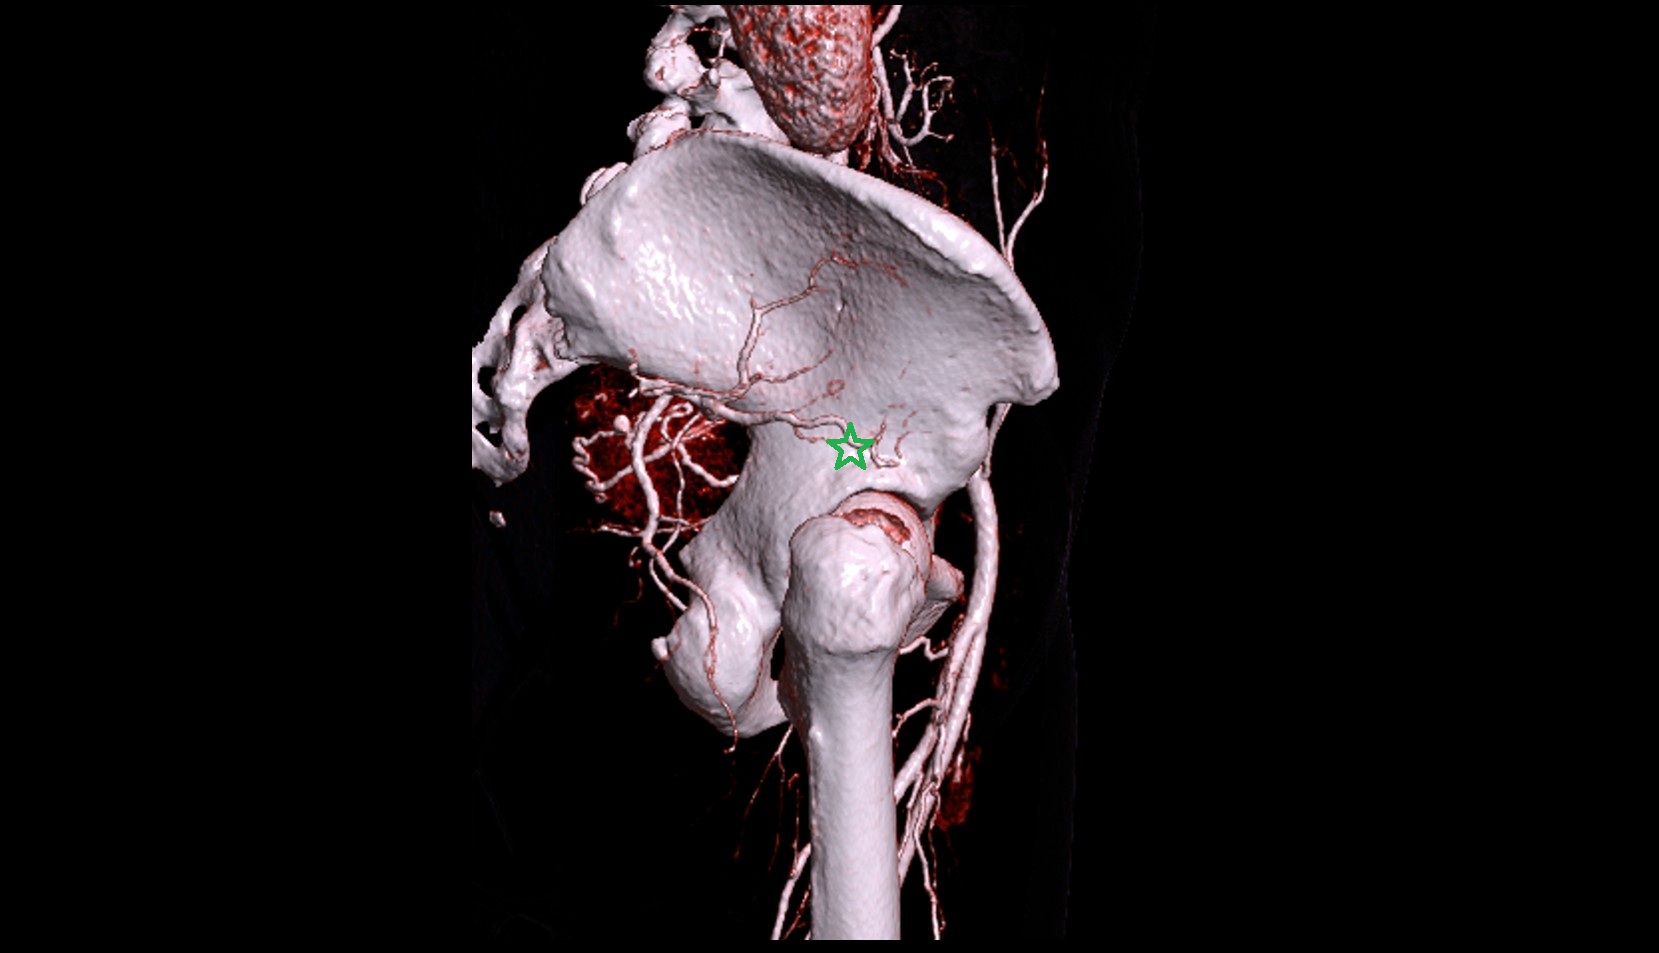

- Abdominal aorta

- Aortic bifurcation

- External iliac artery

- Internal iliac artery

- common iliac artery